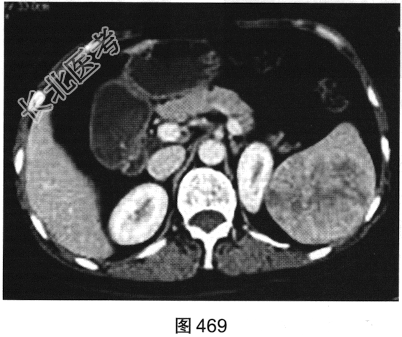

- 多项选择题2.[提示]患者行CT动态增强扫描,如图467~图469所示。对CT图像描述正确的是( )

A、病灶内见条索状钙化灶

B、病灶动脉期无强化

C、CT平扫呈不均匀稍低密度

D、左肾被病灶侵犯

E、病灶门脉期显著强化

F、病灶边界清晰,具有包膜